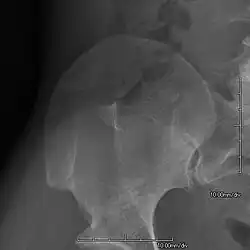

AP radiograph showing a hypoplastic patella in NPS

• Patellar involvement is present in approximately 75% of patients;[5] however, patellar aplasia occurs in only 20%.

• In instances in which the patellae are smaller or luxated, the knees may be unstable.

• The knee joint may appear square.